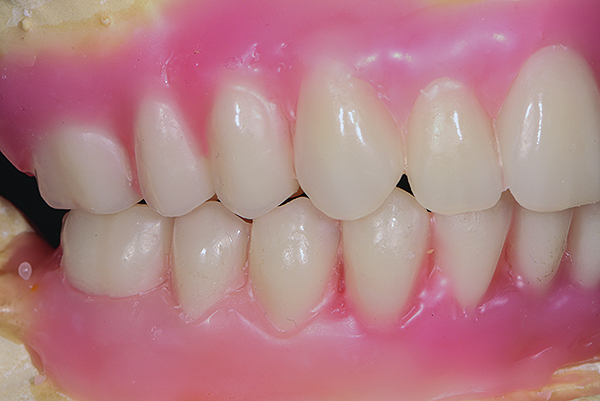

Patient intraoral condition 3 years following delivery of maxillary and mandibular All-on-4 denitive prosthesis.

Figure 20